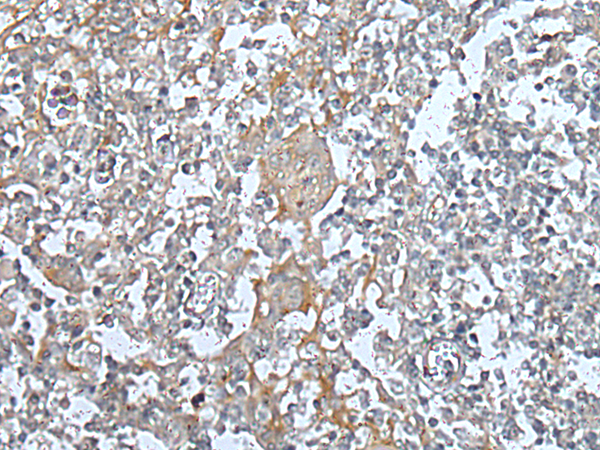

IHC positive control: |

Human tonsil |

IHC Recommend dilution: |

25-100 |